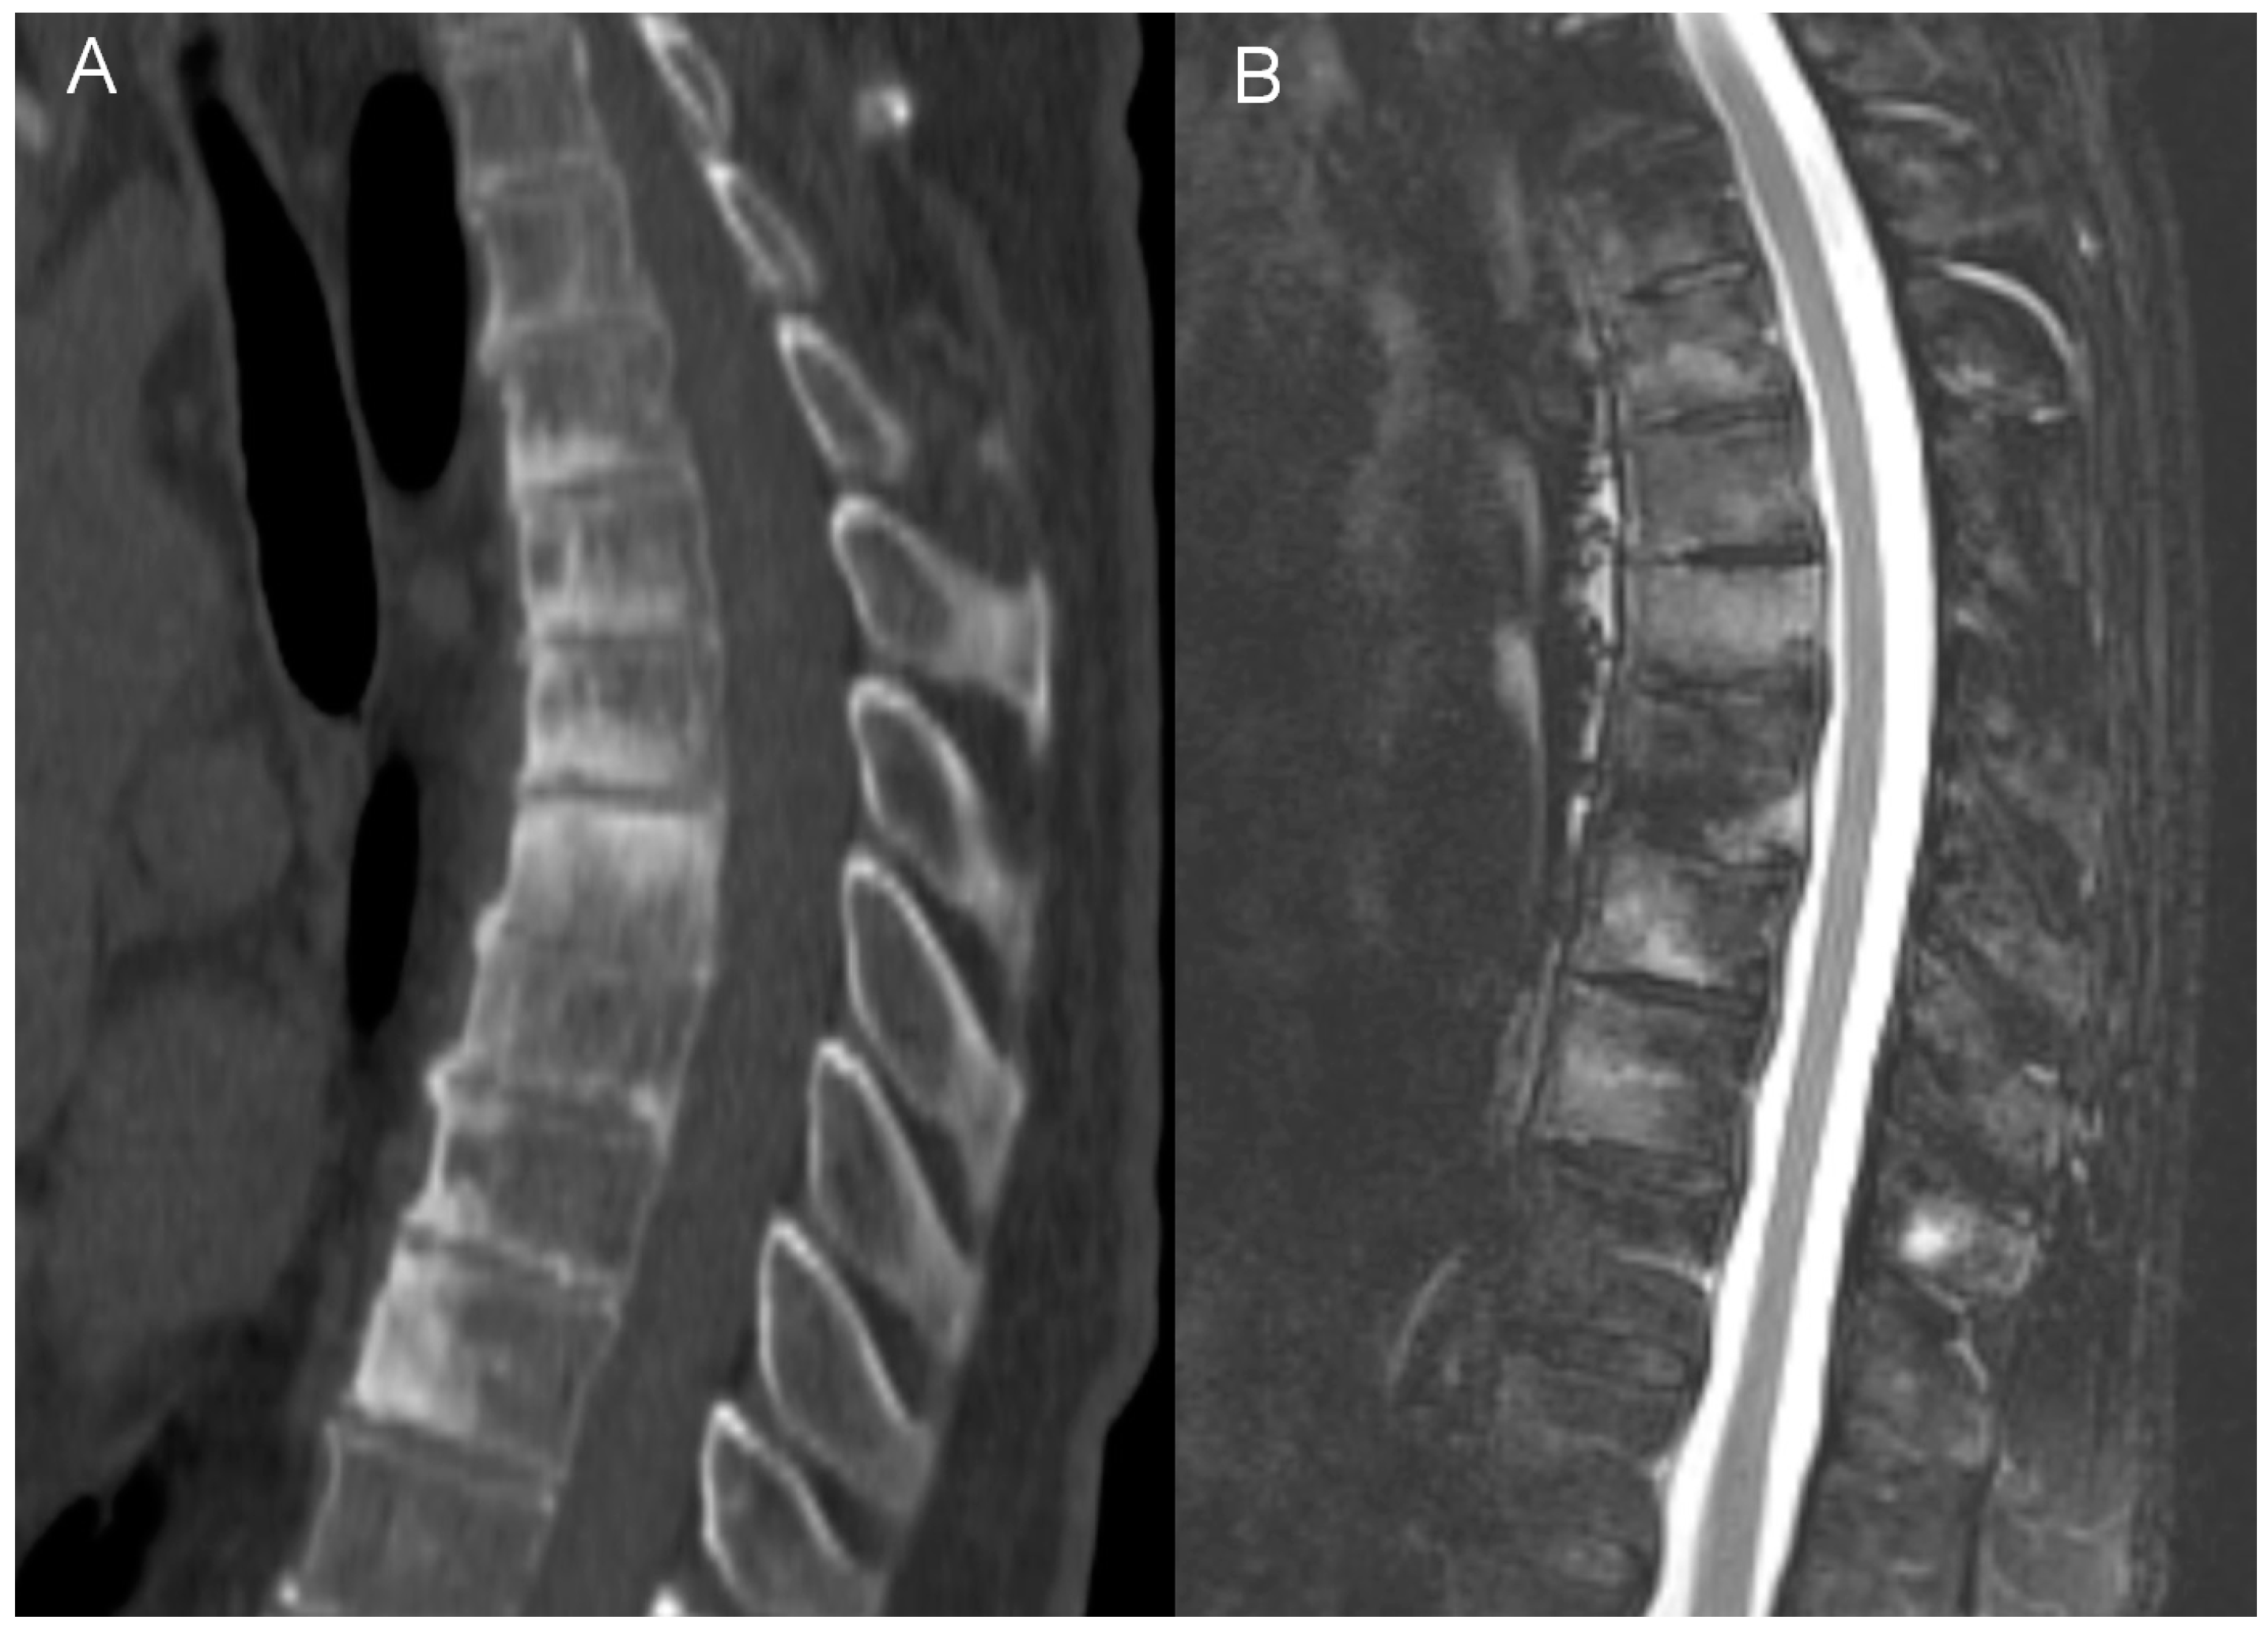

In adults, the main findings were BME, osteosclerosis, endplate irregularities, and a spectrum of ankylosing lesions. Similar to previous publications, the lesions were multilevel and contiguous [21,22,32,33]. Curvilinear/semicircular pattern of BME found in the majority of patients in the study by McGvuran and coworkers was less common in our material three patients); however, both BME and osteosclerosis overlapping BME on plain film/CT were definitely the most striking abnormalities (Figure 4) [22]. We also observed a long persistence of BME that was present through the whole length of follow up, even in patients followed for more than 10 years. On MRI, contrast enhancement was observed in the areas of BME, but also in the linear fashion along the endplates and frequently in the non-ankylosed costovertebral and facet joints. Paraspinal soft tissue involvement was observed in 10 out of 12 patients subjected to MRI (83%), more often than in previous publications [22,34]. In agreement with previous reports, most of the intervertebral discs showed decreased T2 signal corresponding to degeneration rather than the high signal seen in discitis [22]. Vertebral deformities were limited to anterior wedging, most pronounced at the apex of thoracic kyphosis. Ankylosing lesions were prevalent and, as previously reported, showed a progressive character on follow up [35,36]. Anterior bony bridging resembling this observed in diffuse idiopathic skeletal hyperostosis (DISH) was accompanied by intervertebral fusion and facet joint ankylosis. Contrary to previous reports, we have not observed the resolution of hyperostosis once ankylosis was complete [36].

Figure 4.

Imaging findings of the thoracic spine involvement in a 65-year-old patient with SAPHO syndrome. CT (A) shows multilevel, contiguous vertebral osteosclerosis, endplate erosions, and early syndesmophyte formation. MRI (B) shows diffuse and propagating patterns of BME and mild prevertebral soft tissue inflammation.